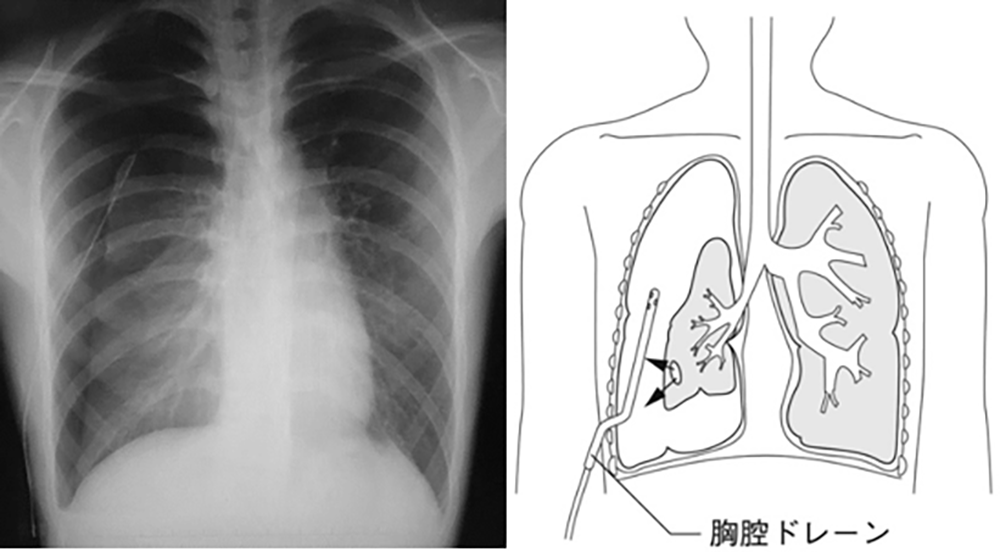

気胸とは、本来空気の存在しない胸腔内に何らかの理由で空気が漏洩・貯留し、肺が虚脱した状態のことを言います。

気胸の診断には、胸部レントゲンや胸部CT撮影を行います。突発する胸痛(時に背部痛)・呼吸苦・咳嗽を主訴に来院された場合、問診と胸部身体所見を行い前述の画像診断で確定診断と治療方針を決定します。

気胸の治療には、外来通院で診られるものから入院を要するものまで様々な病態があります。そのため、当院気胸センターには呼吸器内科・呼吸器外科・救急科の3科の医師が所属しており、それぞれの病態に応じた担当医が気胸の診療を行います。軽度虚脱の場合は安静のみで外来通院による経過観察となります。虚脱が中等度以上(虚脱率20%以上)の場合は、胸腔ドレナージという処置が必要で入院となります。胸腔ドレナージを行っても治らない場合や両側症例、再発症例は手術療法の適応になります。